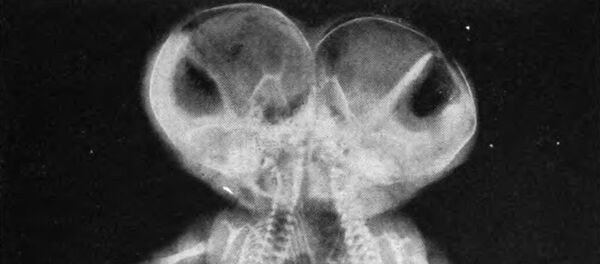

اندام اضافی این کودک پیش از تولد هم در اسکنی معمولی از رحم مادرش هویدا شده بود اما داکتران در ابتدا تصور کرده بودند پای اضافی او، یک دوقلوی انگلی است.

دوقلوهای همسان نیز کمی بیشتر نادر بوده و زمانی رشد میکند یک تخمک بارور تنها در مراحل اولیه بارداری دو قسمت میشود، در دوقلوهای به هم چسبیده نیز این تقسیمبندی در مراحل اولیه به طور کامل انجام نمیگیرد.

در این گونه موارد که بسیار نادر هستند، به جای تقسیمشدن در داخل دیگری به دام میافتد، در این وضعیت جنین محسور با قطعشدن منبع خون مادر در نهایت میمیرد و به عنوان یک دوقلوی انگلی شناخته میشود.